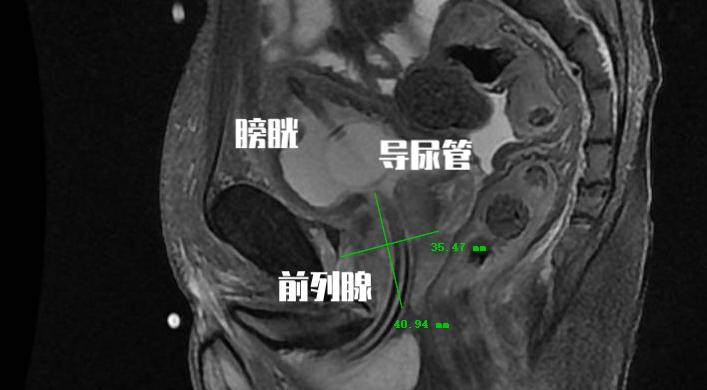

从PSA的分泌来源中我们不难看出,随着前列腺体积增大, 前列腺增生组织也会分泌PSA 。所以对于很多老年男性患者,虽然PSA水平增高,但是在核磁共振检查和前列腺穿刺活检中都最终证实并不是前列腺癌。

前列腺特异性抗原密度(PSAD)是测算血清总PSA值与前列腺体积的比值,正常值≤0.15。比值越高意味着越有可能为具有临床意义的前列腺癌。